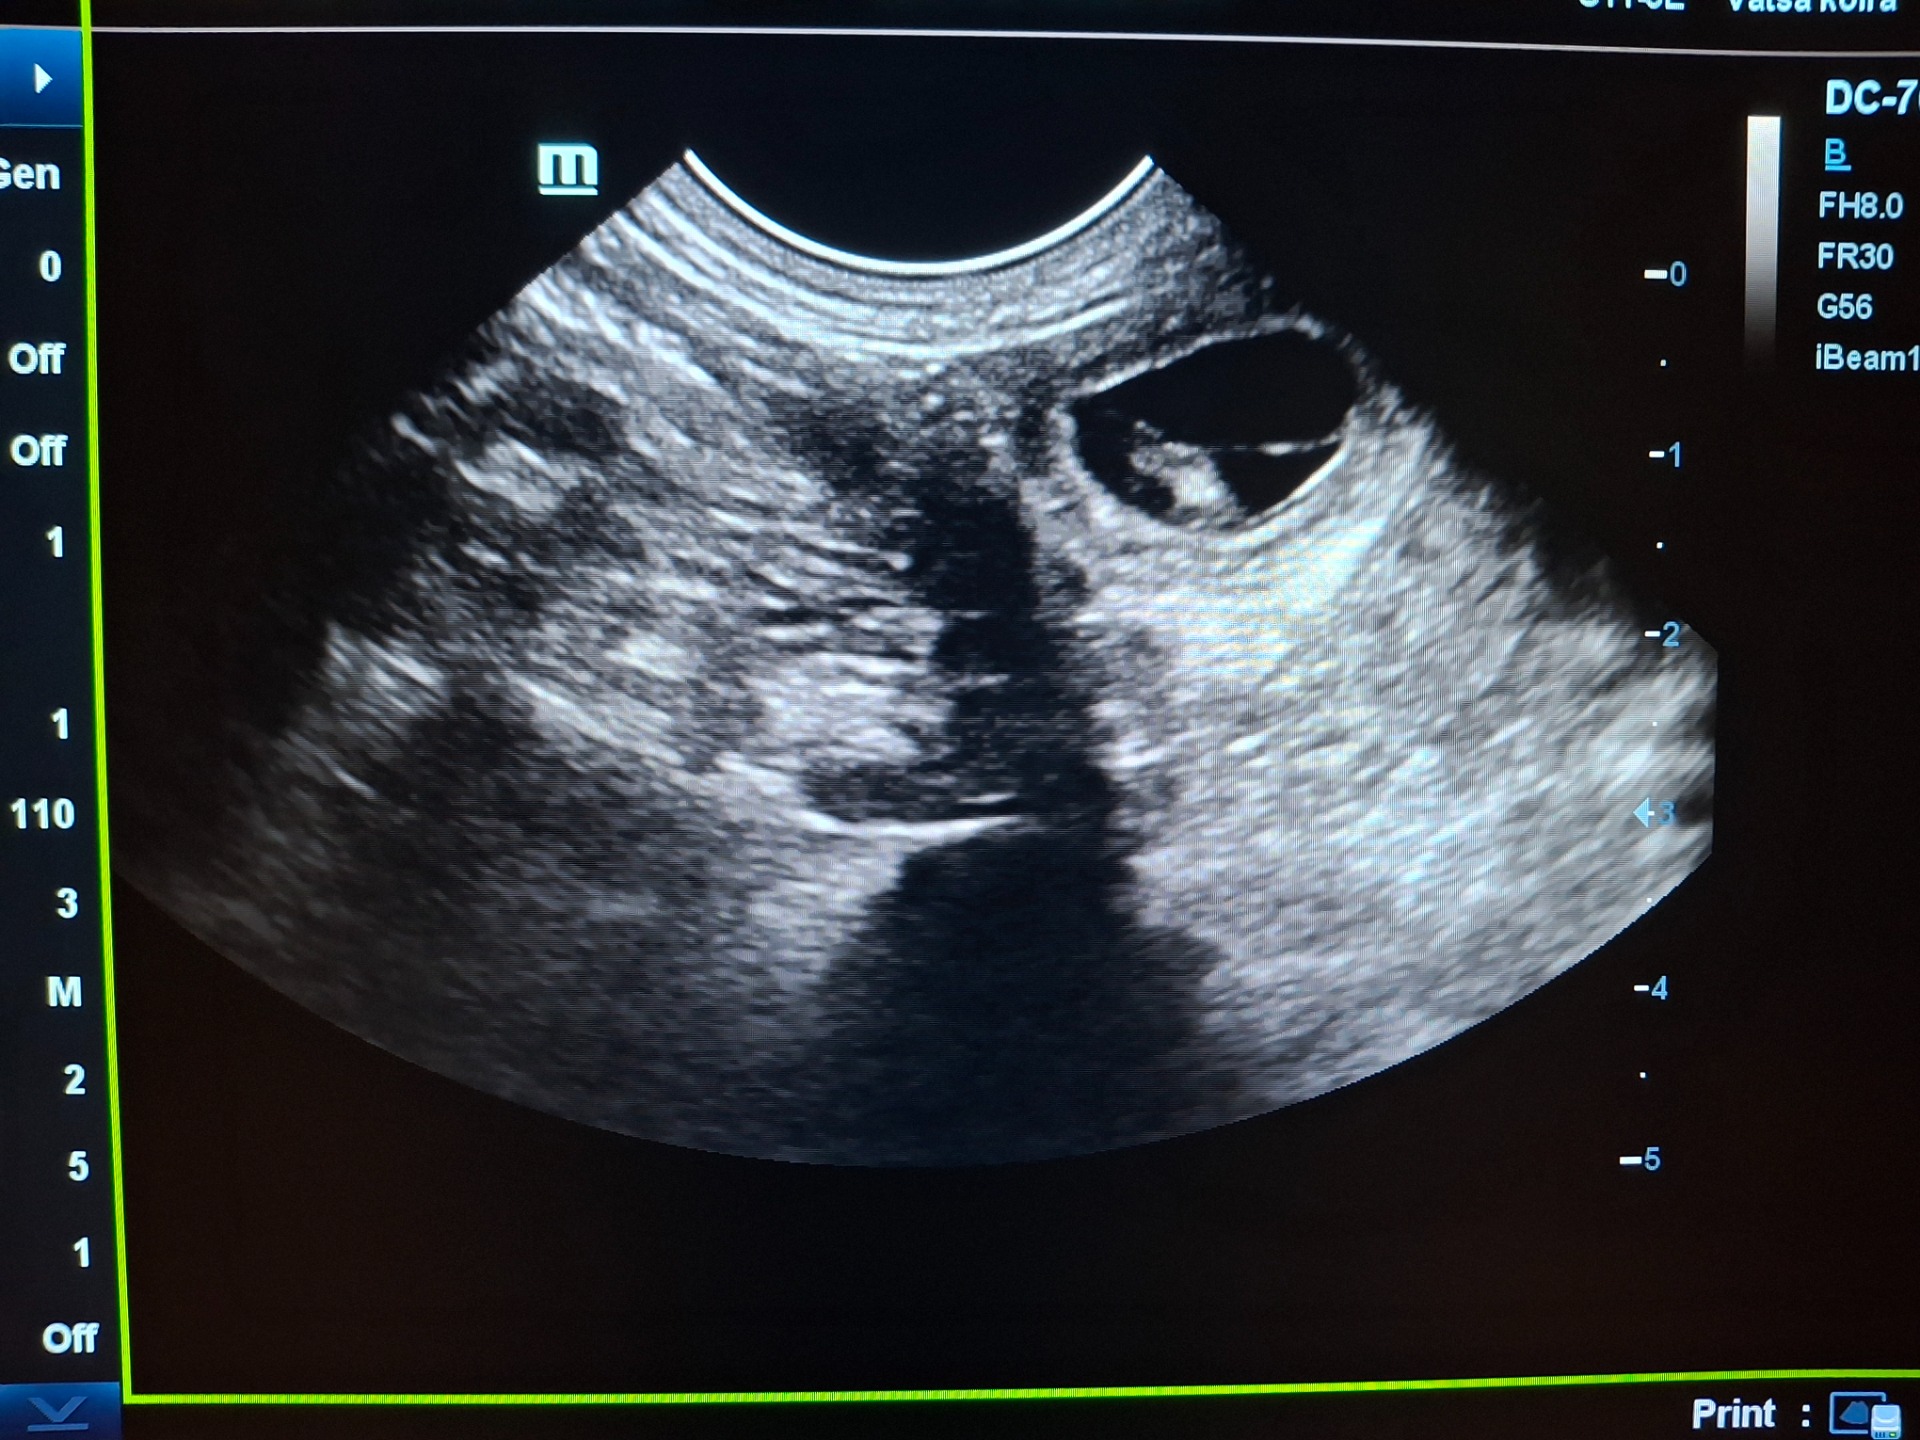

25.11.2025

Lola on ultrattu ja 2 pentua on tulossa varmuudella❤️ Pennut syntyvät joulukuun loppupuolella🥰